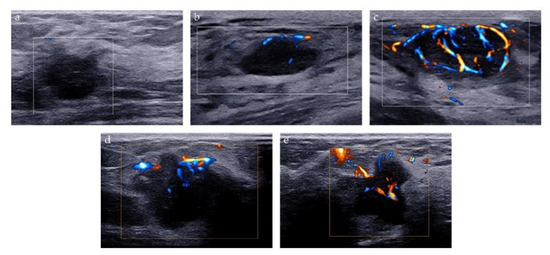

2.2. Ultrasound Image Acquisition

2.3. Ultrasound Image Evaluation